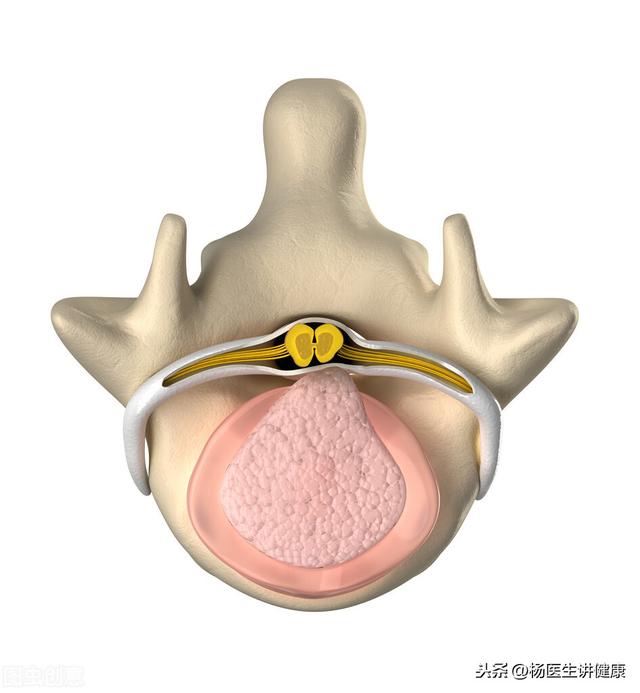

椎間板とは、椎骨と椎骨の間にある組織である。椎骨と椎骨の間には線維輪と髄核があり、髄核を包んでサンドイッチのように椎骨と椎骨の間に固定されている。

椎間板ヘルニアとは、この線維輪が破れ、中の髄核が出て背中側に突出し、脊髄や神経根を圧迫することで、痛みや麻痺などの症状を引き起こすものです。

椎間板ヘルニアとは、椎間板が線維性環状体で髄核を包んでいる不可逆的な状態のことで、サンドイッチのパンのように想像することができる。環状線維は軟骨のような構造で、髄核を包んで体から隔離するだけでなく、人間の背骨の複雑な動きのための機能的なユニットを形成するために、ある程度の弾力性と支持力を提供する機能もある。真の椎間板ヘルニアは、環状線維の断裂によって引き起こされる髄核の突出である。髄核には大きく分けて2つの特徴があり、1つ目は水分を多く含み、ペースト状の髄核をぎゅっと押すことで水分が移動し背骨が動くこと。第二に、髄核は体の三大自己抗原の一つであり、椎間板ヘルニア後の神経刺激痛の主な原因である。自己抗原については、強い酸や塩基など、体に対して強い刺激と腐食性を持つ化学物質と考えることができます。なぜ椎間板ヘルニアになるのか?長年の誤った姿勢が髄核の偏位を引き起こし、長年の椎間板内の不均等な圧力、そして最終的に線維性環状体の破裂が原因であり、暴力が線維性環状体の破裂を引き起こし、髄核の破裂も原因であるが、前者の原因の方がクリニックでは一般的である。椎間板は、線維性環状組織の損傷の程度によって、変性、膨隆、突出がみられ、髄核が完全に流れ出ることを脱出といい、脱出した髄核は脊柱管内をさまよい、より危険な状態になります。水分を多く含む髄核の特性から、椎間板ヘルニアの初期段階は、髄核の水分が吸収され、形態的な崩れがあり、神経に刺激を与えなければ自然症状が緩和されるため、保存的に治療することで良い結果が得られます。また、髄核の化学的性質は、最終的に髄核が石灰化することで緩和される。また、髄核は腐食性があるため、裂け目で突出していると、裂け目はどんどん大きくなるばかりで、治りきらず、最終的には突出するという悪循環に陥ります。保存的治療とは、通常、発作が起きている間は安静にし、消炎鎮痛剤、筋弛緩剤、ホルモン剤などで症状を和らげることです。2、腰椎を支えることは、腰椎の筋肉を萎縮させ、腰椎の症状をさらに悪化させるので勧められない。3、すべてのマッサージ、仙骨療法、椎骨内注射、さらに小さな針ナイフは病気にダメージを与えるので、治療にはお勧めできません。推拿はヘルニアを悪化させる可能性があり、仙骨療法、椎骨内注射は局所の癒着を引き起こし、症状を悪化させたり、その後の手術に支障をきたす可能性があります。小さな鍼の有効性は、部外者にはよく知られていない多くの理由によって、さらに不確かである。もちろん、理学療法、マッサージ、鍼治療、その他の筋肉の緊張を和らげる方法はまだ使える。最後に、手術についてですが、神経症状が緩和されない状態が続いたり、排尿・排便の衝撃、母趾、足関節背側伸展障害などの馬尾症候群の症状が出現した場合には、手術治療を行わなければなりませんが、腰椎不安定症などの疾患と組み合わせて手術治療を検討する必要があり、具体的な手術方法は専門医の意見を聞くことをお勧めしますが、腰椎椎間板ヘルニアの手術はどのような手術であっても、修復ではなく、修復です。これは根本的な違いです。

リカバリーが難しい!これは椎間板の構造によって決まります。腰椎椎間板は全体ではなく、内側の髄核と外側の線維性環状骨からなり、その後ろに靭帯があります。したがって、椎間板ヘルニアは椎間板全体のヘルニアではなく、椎間板から髄核が徐々に「はみ出した」状態です。初期の段階では、髄核の周りの線維輪は破壊されていないので、腰椎椎間板「膨隆」と呼ぶことができ、後期になると、髄核が周りの線維輪を突き破り、脊柱管にまで入り込んで神経を圧迫すると、腰椎椎間板「ヘルニア」となります。したがって、腰椎椎間板ヘルニアが起こるということは、腰椎椎間板の周りの線維輪の構造が「ヘルニア」と同じように破壊されたということであり、ヘルニアになった髄核は非常に戻りにくいのです。また、髄核を包んでいる線維輪は血行が悪いだけでなく、治りも悪いので、髄核がかろうじて回復しても、また簡単にヘルニアになってしまいます。